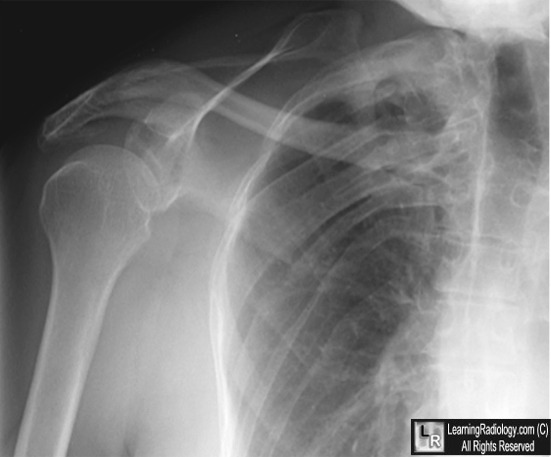

Incidental Finding Of Unilateral Isolated Aplasia Of Serratus ...

Winged Scapula Chest Radiograph Incidental Finding of Unilateral Isolated Aplasia of Serratus Anterior Congenital elevation of the scapula. J Bone Joint Surg Br 1972;54:395-408 6. Hegde HR, Shokeir MH. Posterior shoulder girdle abnor- ... Return Document